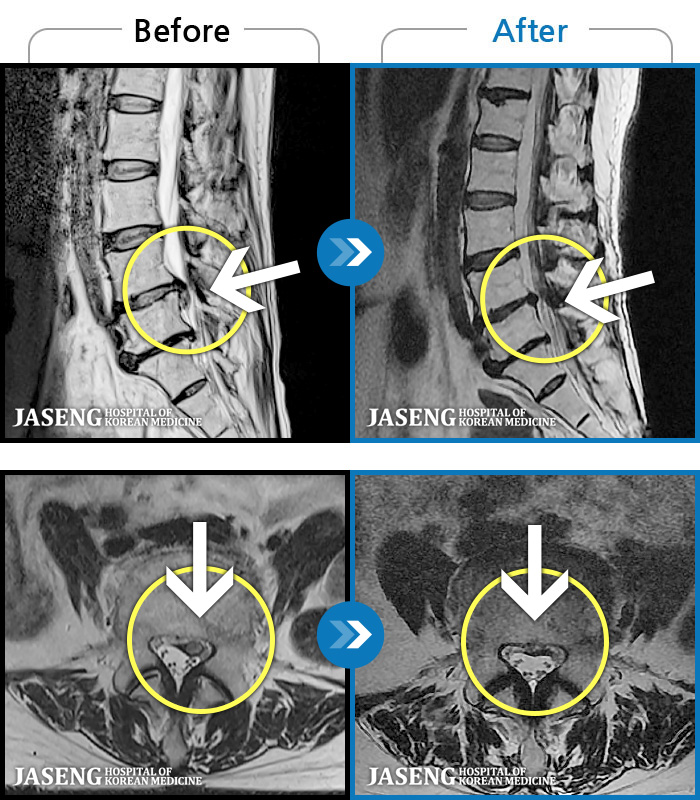

MRI ġ

1,240 MRI ũ ʸ Ȯϼ.